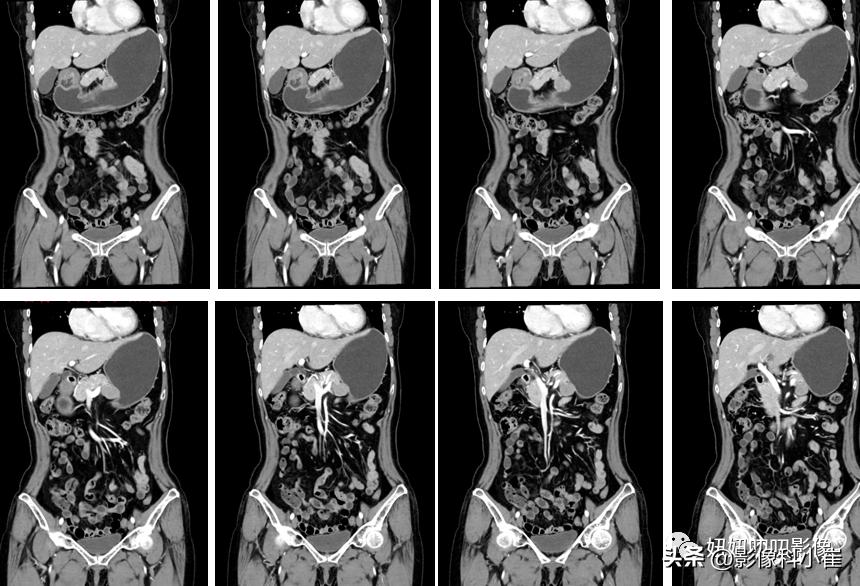

图像:

胃腔充盈尚可,胃底大弯侧脾胃间隙见类圆形软组织密度灶,边界清,大小约 2.5X2.3cm,增强扫描呈渐进性明显强化,邻近胃粘膜线未见明显中断。